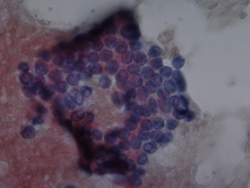

요세포 검사상의 악성세포 소견

2009.08.20